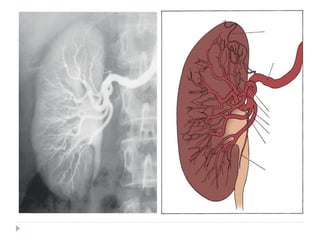

Renal Vasculature

The renal pedicle classically consists of a single

artery

and a single vein that enter the kidney via the renal

hilum . These structures branch from the aorta and

inferior vena cava just below the superior mesenteric

artery at the level of the second lumbar vertebra. The

vein is anterior to the artery. The renal pelvis and

ureter are located farther

posterior to these vascular structures.

Renal Artery

the right renal artery leaves the aorta and progresses

under the IVC toward the right kidney. The

left renal artery courses almost directly laterally to the left

kidney.

Given the rotational axis of the kidney , both renal

arteries move posteriorly as they enter the kidney. Also,

both arteries have branches to the respective adrenal

gland, renal pelvis, and

ureter.

-Upon approaching the kidney, the renal artery splits into

four or more branches. These are the renal segmental

arteries . Each segmental artery

supplies a portion of the kidney with no collateral

circulation between them . Thus occlusion or injury to a

segmental branch will cause segmental renal infarction.

Generally,

the first and most constant branch is the posterior

segmental branch.

-Typically there are four anterior branches, which from

superior to inferior are apical, upper, middle, and lower.

The relationship of these segmental arteries is important

because the posterior segmental branch passes

posterior to the renal pelvis while the others pass

Once in the renal sinus, the segmental arteries branch into

lobar arteries, which further subdivide in the renal parenchyma

to form interlobar arteries . These interlobar arteries

progress peripherally within the cortical columns of Bertin, thus

avoiding the renal pyramids but maintaining a close association

with the minor calyceal infundibula. At the base (peripheral edge)

of the renal pyramids, the interlobar arteries branch into arcuate

arteries. Instead of moving peripherally, the arcuate arteries

parallel

the edge of the corticomedullary junction. Interlobular

arteries branch off the arcuate arteries and move radially, where